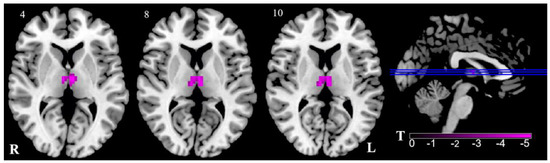

In the VM group, only the ALFF values in the thalamus were bilaterally decreased, as compared with those in the control group, as shown in Figure 1 and Table 2.

Figure 1.

Regional ALFF reduction in VM patients in contrast to HC. Pink signifies decreased ALFF. The axial image was overlaid on the transverse section of the MNI-152 standard anatomical image. Blue line represents the layers in the sagittal. Numbers indicate z slice. The color scale denotes the t-value. R, right; L, left.